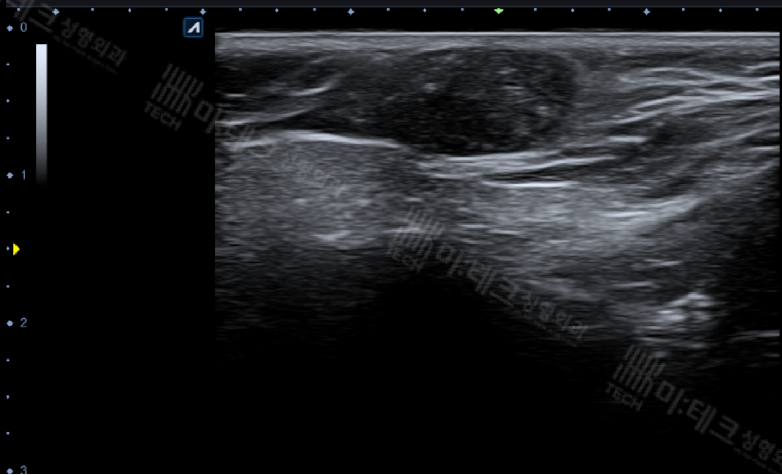

정확한 진단을 위해 초음파 검사를 시행했습니다.

약 1.5cm가량의 피지낭종과 유사한 정도의 음영으로 보이는데,

아직 많이 딱딱해지지 않은 상태로 보입니다.

딱딱한 경우보다는 좀 더 쪼개서

꺼내기 용이한 상태라고 생각하면 될 것 같습니다.

(많이 딱딱해지면 밑으로 그림자가 상당히 남게 됩니다.)